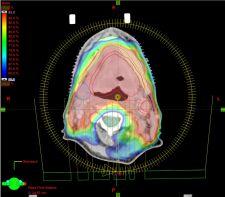

The Eclipse treatment planning system is a comprehensive solution designed to simplify modern radiation therapy planning for all kinds of treatment, including 3D conformal, intensity-modulated radiation therapy (IMRT), image-guided radiotherapy (IGRT), RapidArc volumetric modulated arc, electron, proton and brachytherapy treatments.

3D conformal planning tools in Eclipse are combined with interactive dose-volume optimization for reportedly fast, flexible and accurate IMRT planning. Automatic optimization of beam geometry simplifies the task of selecting the best beam angles for fixed-beam IMRT. Eclipse also incorporates a Smart Segmentation automatic contouring feature, the first fully automatic tool that uses intelligent software to identify and outline, within diagnostic images, organs and other structures to be irradiated or protected during treatment.